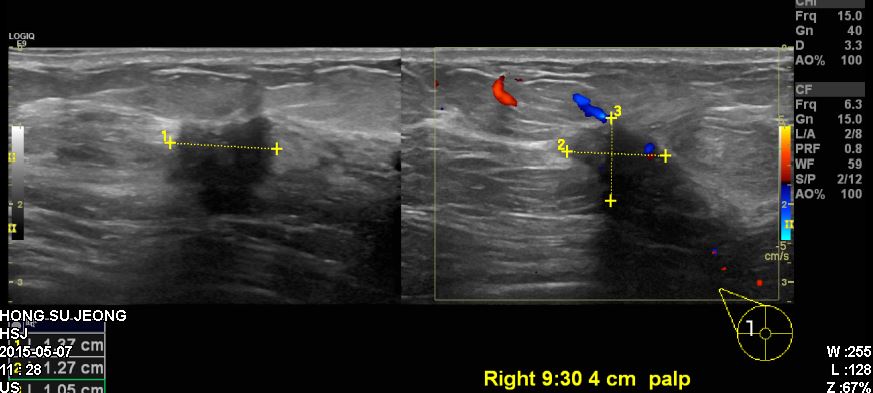

건강검진상 이상소견으로 내원하신 50대 여성분으로 본원에서 초음파 시행 후

우측 9 :30 방향에서 4cm 떨어진 거리의 혹 조직검사시행 하였으며,

우측 침윤선 유관암 진단 되었습니다.